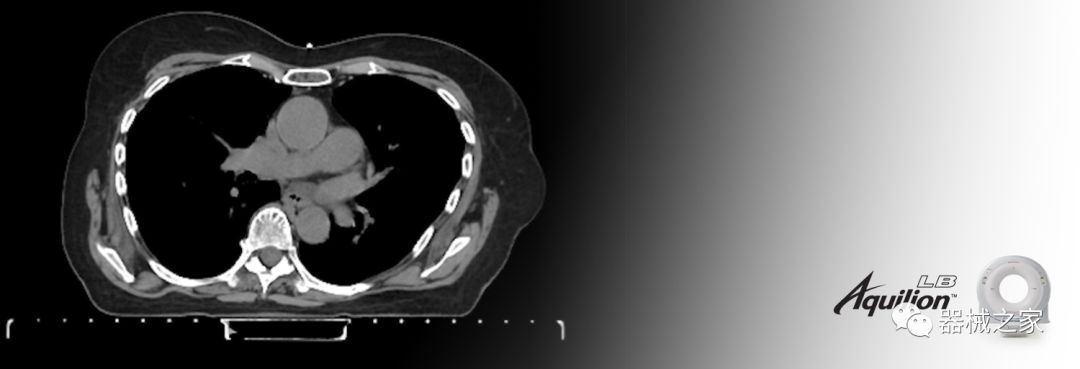

在以患者為中心的放射腫瘤學(xué)領(lǐng)域,計(jì)算機(jī)斷層掃描(CT)的可訪問性,可重復(fù)性和靈活性至關(guān)重要。為了建立這些價(jià)值,佳能醫(yī)療系統(tǒng)美國公司現(xiàn)在正在擴(kuò)大其放射腫瘤學(xué)CT模擬產(chǎn)品,包括Aquilion Prime SP和Aquilion Lightning 80高級(jí)CT系統(tǒng)。除了Aquilion LB之外,Aquilion Prime SP和Aquilion Lightning 80現(xiàn)在還包括放射治療(RT)選項(xiàng),可為腫瘤學(xué)規(guī)劃提供高質(zhì)量的CT成像和精密工具。

佳能醫(yī)療的Aquilion Lightning 80掃描儀還以緊湊,經(jīng)濟(jì)的包裝提供高質(zhì)量的成像。Aquilion Lightning 80旨在可靠,高效地運(yùn)行,在繁忙的環(huán)境中生成高質(zhì)量的圖像。

Aquilion LB專為滿足腫瘤學(xué)挑戰(zhàn)而設(shè)計(jì),同時(shí)優(yōu)先考慮患者護(hù)理。Aquilion LB的內(nèi)徑為90 cm,能夠幫助復(fù)雜的患者設(shè)置并提高患者的舒適度。CT模擬定位可以輕松鏡像放射治療定位,更加自信。該系統(tǒng)采用0.5 mm x 16排(32層)PUREViSION探測(cè)器技術(shù),70 cm視野,AIDR 3D和SEMAR技術(shù)。